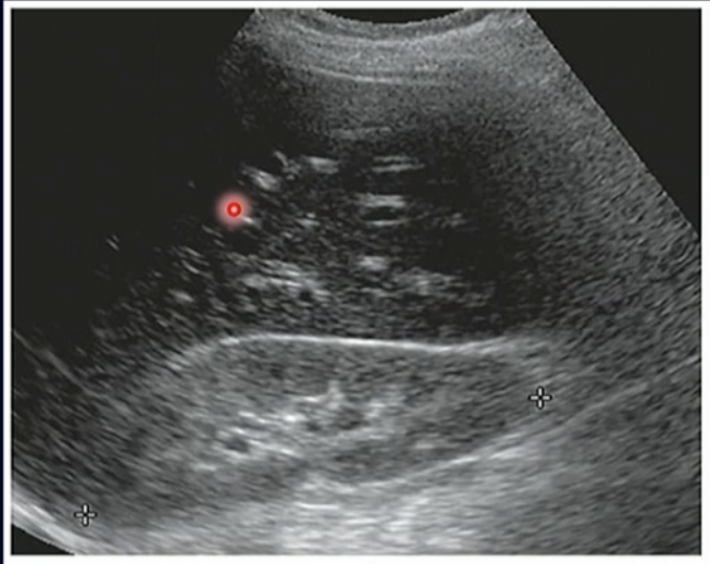

Path?

Urolithiasis in the Rt Middle Pole of Kidney

Staghorn Calculus

What is this?

Moderate Hydronephrosis (As it is one coherent structure there is not segmented Echogenic Structures)

Parapelvic Cysts (as it is segmented)

Severe Hydronephrosis